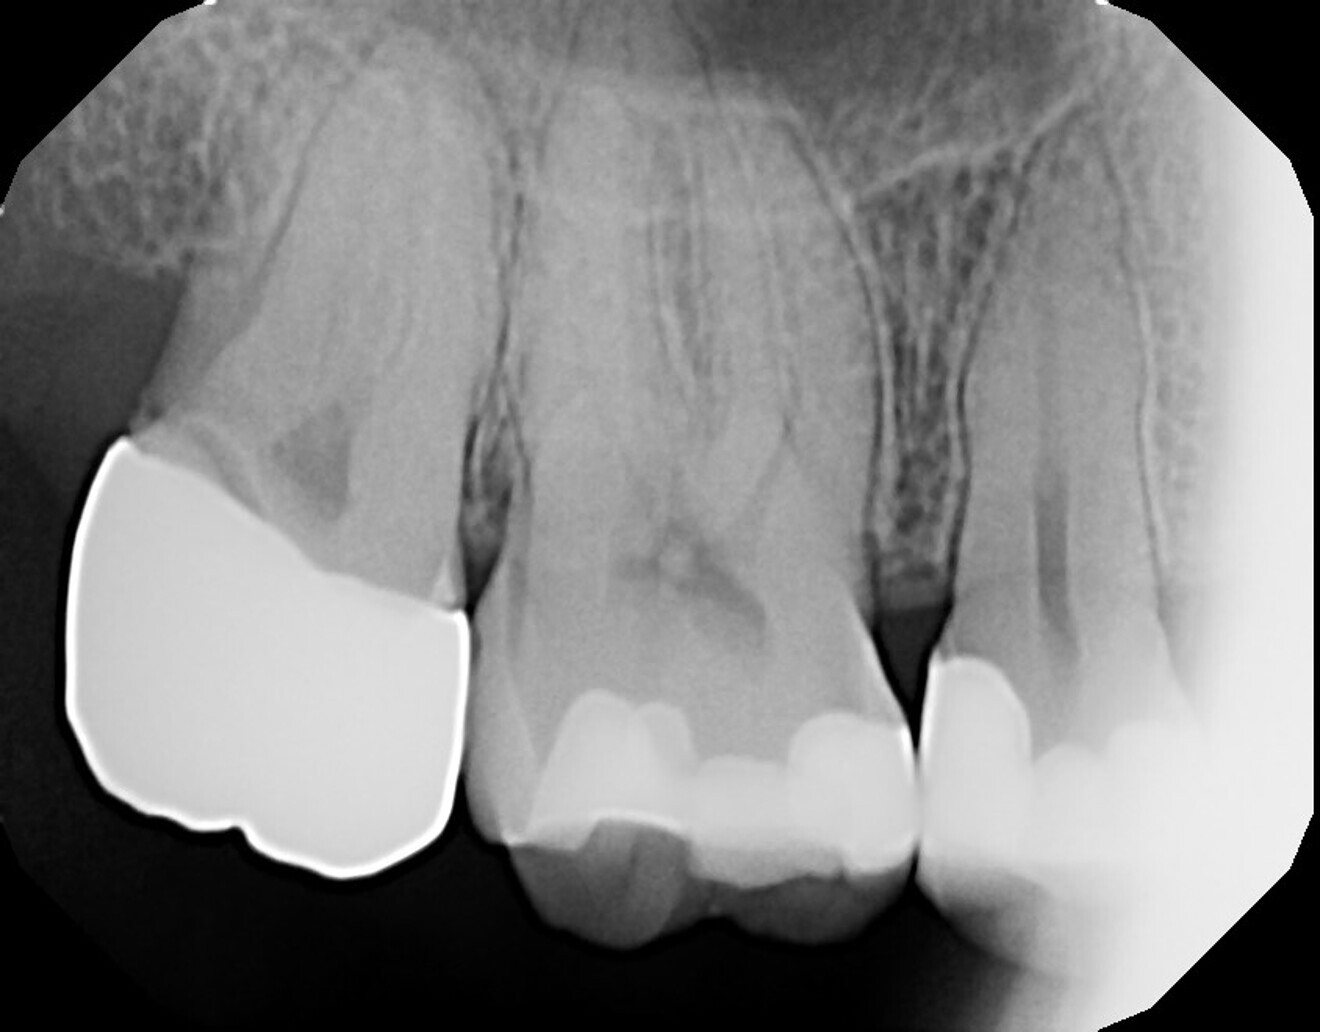

A 53-year-old female patient presented with the complaint of pain in the maxillary left quadrant. Clinical examination noted a missing lingual cusp on the second premolar as well as caries, and a periapical radiograph was taken (Fig. 13). Deep caries was confirmed radiographically, and most of the crown was radiolucent, indicating extensive caries. The outline of the coronal pulp could be observed radiographically, and a lack of periapical pathology was noted. The tooth was tested with cold to verify that the pulp was vital. A mild reaction was noted when cold was applied that immediately resolved when cold was removed from the tooth, indicating that the tooth was vital. The patient was informed that pulpal exposure was expected from caries removal and endodontic treatment would be necessary. After the anticipated endodontic treatment, the tooth would be treated with a post and core and restored with a complete crown. The patient agreed to the recommended treatment.

The patient was seen on recall at four weeks after laser treatment and continued to report a lack of sensitivity to temperature or occlusion. A periapical radiograph was taken, and no periapical radiolucency was noted, indicating that laser treatment of the pulpal exposure had successfully aided in avoiding endodontic treatment (Fig. 17).

A 29-year-old female patient presented with the complaint of sensitivity in the maxillary right quadrant and requested a second opinion on the possible need for endodontic treatment that her prior dentist had recommended, owing to deep caries. She reported hot and cold sensitivity and lingering cold sensitivity of the second premolar. A periapical radiograph was taken, and it showed caries in teeth #15 and 14 on the mesio-occlusal aspect and in close proximity to the pulp in tooth #15, but no periapical pathology was noted (Fig. 18). The patient was informed of the possibility of the need for endodontic treatment and that this would be determined when the caries was removed and if a pulpal exposure was noted. Should a pulpal exposure not present, laser pulp capping could be performed and the tooth restored, but presentation of increasing tooth sensitivity at a later date would indicate that endodontic treatment may be required. The patient agreed to proceed with treatment.

The patient was seen at routine prophylactic recall appointments and continued to report an absence of sensitivity in the maxillary right quadrant. A periapical radiograph at five years after treatment demonstrated an absence of periapical pathology (Fig. 19).

Fig. 18: Initial periapical radiograph demonstrating caries on the mesio-occlusal aspect of teeth #15 and 14 and an absence of periapical pathology.

Fig. 19: Periapical radiograph at five years after laser pulp capping and restoration of tooth #15, demonstrating an absence of periapical pathology.